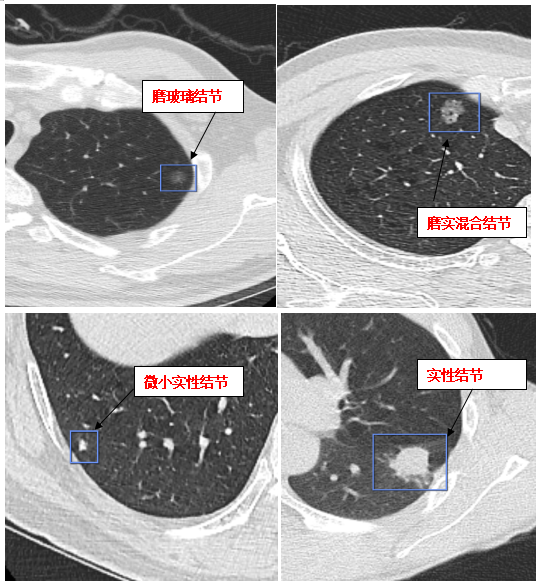

结节的大小、密度、形态等与结节的良、恶性具有一定程度相关性。肺结节有几种分类:

1、大小:直径<5mm称为微小结节;直径5mm-10mm称为小结节;直径11mm-30mm称为结节。

2、密度:分为实性结节和亚实性结节(包括纯磨玻璃结节pGGN和混合磨玻璃结节mGGN)。